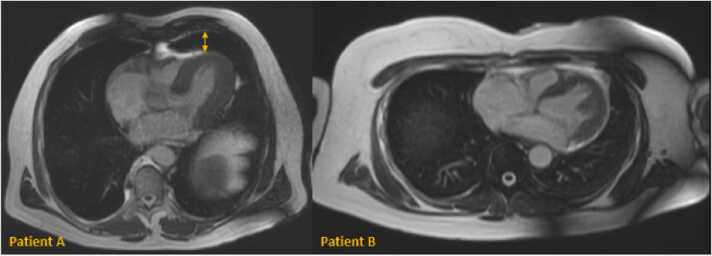

Results: Twenty-one patients (7 female) were included (age: 45.4 ± 19.7 years; body mass index: 27.6 ± 5.5 kg/m2). DUS mean trigger delay was 128 ± 28 ms. DUS mean trigger jitter was 23 ± 13 ms. Overall image quality showed no difference between ECG and DUS gating (e.g., short axis: 5 [interquartile range (IQR) 3-5] vs 4 [IQR 3.5-5]; P = 0.21). Quantitative analysis revealed no differences between ECG and DUS gating: LVEF (53.2 ± 9.2% vs 52.3 ± 9.1%; P = 0.18; ICC 0.97 [95% confidence interval [CI] 0.93-0.99]), LVEDVI (84.5 ± 15.8 mL/m2 vs 83.3 ± 15.8 mL/m2; P = 0.06; ICC 0.99 [95% CI 0.98-1.00]), RVEF (52.8 ± 8.0% vs 51.6 ± 7.2%; P = 0.06; ICC 0.96 [95% CI 0.89-0.99]), and RVEDVI (80.8 ± 17.6 mL/m2 vs 80.9 ± 16.5 mL/m2; P = 0.91; ICC 0.98 [95% CI 0.96-0.99]). In one patient with a prominent lingula of the lung image quality was non-diagnostic with DUS gating.